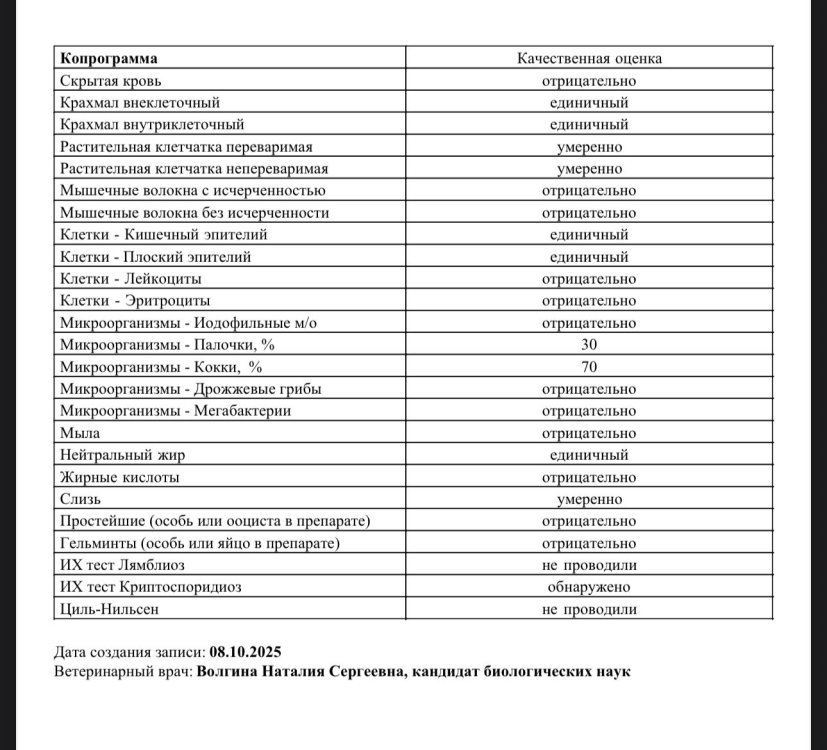

Вот как-то так сегодня вчера но он такой зеленый, тк по факту еще очень голодный Когда ел зерно, цвет был стандартный, но порции помёта были очень большие На повторную микроскопию сдать смогу только завтра хочу динамику посмотреть но думаю, что амоксиклав отменяю (уже более 14 дней даю) А вот что делать не знаю Моя теория, что у лямблий и/или криптоспоридий резистентность к метронидазолу возникла, они бушуют и ослабляют иммунитет - пищеварение в частности исхожу от того, что раньше метронидазолом эта проблема решалась сразу есть стоп-кокцид, думаю его дать завтра наконец-то приедет нутриберд, у меня с ним отношения лучше складываются, чем с кашами 🫠 Вот прям свежий помет @маленький принц Это анализы от 08.10